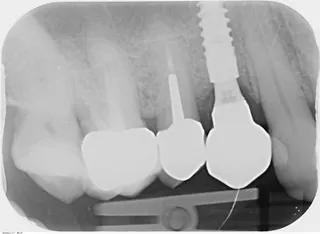

Basierend auf den klinischen und röntgenologischen Befunden wurde eine Periimplantitis in Regio 14 diagnostiziert. Der Behandlungsplan sah einen kausalen Behandlungsansatz vor und beinhaltete die Beseitigung des Infektionsherds. Im Bereich des Abszesses wurde eine kleine Inzision gesetzt. Die Läsion wurde mit Povidon-Jod und Chlorhexidin gespült und mit einer Oxytetracyclin-Hydrocortison-haltigen Gaze abgedeckt. Die prothetische Zahnkrone wurde vom Implantat geschraubt, in die Zahnfleischtasche wurde Guttapercha eingebracht. Anschliessend wurde eine Röntgenaufnahme angefertigt, um den Ursprung der Läsion zu bestätigen. Die Aufnahme bestätigte einen bukkalen Infektionsherd, der mit dem Implantat in Regio 14 assoziiert war (Abb. 2). Die Behandlungsoptionen wurden mit der Patientin erörtert, wobei der ortsständige Knochenverlust sowie ästhetische Aspekte berücksichtigt wurden.

Abb. 02